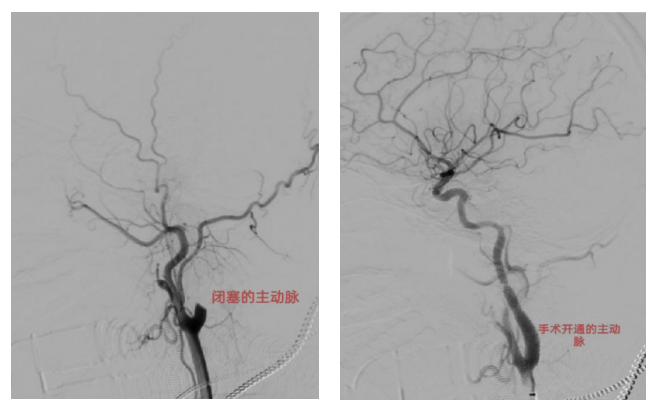

救治团队当即启动脑梗死规范化急救流程,各项工作紧张而有序推进:急诊溶栓治疗迅速落地,从患者入院到接受溶栓仅用时25分钟,创下高效救治纪录;同时紧急联动介入室、麻醉科,每一次沟通都紧扣“患者25岁,务必最快!”的核心诉求,为手术抢占宝贵时间。在多学科默契配合下,张涛介入团队顺利为患者实施急诊取栓术。术中发现,患者病因是颈内动脉夹层引发的远端栓塞,属于临床少见的复杂串联病变,取栓操作难度极大。团队凭借多年积累的介入诊疗经验和精准操作技巧,成功取出血栓,闭塞血管瞬间开通,脑血流完全恢复,为患者保住了大脑功能。